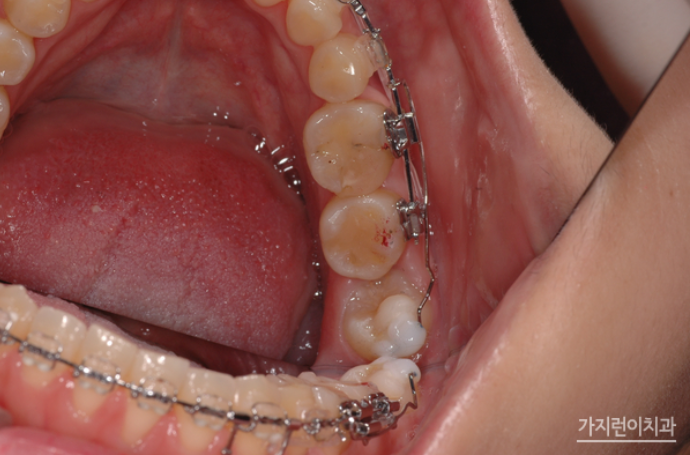

해당 환자분의 경우는 사랑니를 어금니로 대체하는 교정을 계획했었는데요. 위 사진을 보면 사랑니를 세우면서 임플란트를 식립하지 않고 발치 공간을 닫았습니다. 하악 좌측의 사랑니를 효과적으로 세우기 위해 modified bonded cantilever (MBC) spring을 사용했는데요.

상하악 중심선도 잘 맞추었고 교합도 정상교합으로 맞춘 것을 볼 수 있습니다. 하악 사랑니도 잘 세워진 것을 눈으로 확인할 수 있을 정도가 되었는데요. 더 쉽게 보기 위해 교정 전후의 엑스레이 사진도 확인해보겠습니다.